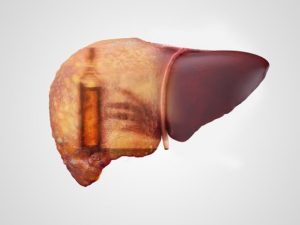

You know all the healthy lifestyle habits necessary to keep your heart healthy, lower your blood pressure, keep your brain sharp, your digestion moving smoothly, and to keep your bones and muscles strong, but do you know what to do to keep your liver healthy? The liver is a very important organ that is involved with over 500 functions, yet many of us ignore it.

You know all the healthy lifestyle habits necessary to keep your heart healthy, lower your blood pressure, keep your brain sharp, your digestion moving smoothly, and to keep your bones and muscles strong, but do you know what to do to keep your liver healthy? The liver is a very important organ that is involved with over 500 functions, yet many of us ignore it.

There are numerous threats to the liver, but many of us don’t take the time to learn how to keep our liver healthy. You may not know this, but a lot of health problems actually stem from the liver, so a healthy liver may be the secret to overall good health.

Diet affects the liver because eventually, everything we take in makes its way through the liver. The liver is responsible for removing toxins and metabolizing substances so that the body can use them. Therefore, you don’t want to eat bad food that can make your liver sick. Instead, opt for healthy food choices, avoid saturated and trans-fat, reduce your alcohol intake, and stock up on vegetables.

Exercise regularly. Yes, your liver can also benefit from regular exercise just like all your other organs. This is because fat can accumulate around the liver, leading to disease. Therefore, regular exercise helps your burn off fat. Furthermore, exercise is a stress reliever and stress is another enemy of the liver.